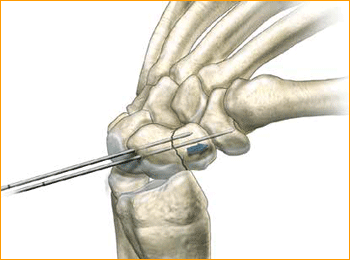

Volar Scaphoid Technique for 2.5 mm, 3 mm, 3.5 mm and 4 mm Headless Compression screws.

1. Approach and Needle Insertion

The procedure can be carried out using the volar traction approach or using a conventional volar type approach with the arm supine on a hand table. The volar traction approach facilitates reduction of a displaced fracture and permits arthroscopy to ensure accuracy of the reduction.

Fluoroscopy is used throughout.

The entry point is then located using a 12 or 14 gauge IV needle introduced on the antero-radial aspect of the wrist just radial to and distal to the scaphoid tuberosity. This serves as a trochar for the guide wire and is a directional aid to establish a central path along the scaphoid. The needle is then insinuated into the scaphotrapezial joint, tilted into a more vertical position and the position is checked on the under image

intensifier. By gently levering on the trapezium this maneuver brings the distal pole of the scaphoid more radial and thus ultimately facilitates screw insertion. The entry point should be approximately 1/3 the way across the scaphoid from the tuberosity in the A/P plane and central in the lateral plane.

2. Guide Wire Insertion

Pass the guide wire through the needle and drill it across the fracture, continually checking the direction on the image intensifier and correcting as necessary, aiming for the radial aspect of the proximal pole. It is extremely important not to bend the guide wire and any adjustments in direction should be made using the needle as a guide rather than attempting to alter the line of the guide wire alone.

3. Determine Screw Length

Advance the guide wire to stop just short of the articular surface as the wire should not breach it at this stage. The position, alignment and length are checked once more. Make a simple stab incision at the entry point of the wire, and deepen this down to the distal pole of the

scaphoid using a small hemostat and blunt dissection.

Determine the length of the screw either with the appropriate depth gauge or by advancing a second guide wire of the same length up the distal cortex of the scaphoid and subtracting the difference between the two. When using the volar approach, the correct screw size is 2–4 mm shorter than the measured length so as to ensure that the proximal tip of the screw is fully buried below the cartilage and the cortical surface.

4. Advance Guide Wire

Advance the guide wire through the proximal pole of the scaphoid so as to exit on the dorsal aspect of the wrist. This is a precautionary measure to minimize the risk of inadvertent withdrawal of the wire during the reaming process and screw insertion and to facilitate removal of the

proximal portion if the wire were to break. A second de-rotation wire can then be inserted in those cases where it is felt that there is a possibility of rotational instability of the fracture.

5. Drill

Remove the 12 gauge needle and pass the Cannulated Profile Drill over the wire using either a power drill or by hand stopping 1–2 mm short of the articular surface. The long drill is recommended to mitigate the effects of varying bone density and distraction upon screw insertion.

6. Advance Self-Tapping Screw

The self-tapping screw is then advanced over the guide wire and the wire removed. Compression can then be confirmed radiographically on the image intensifier.